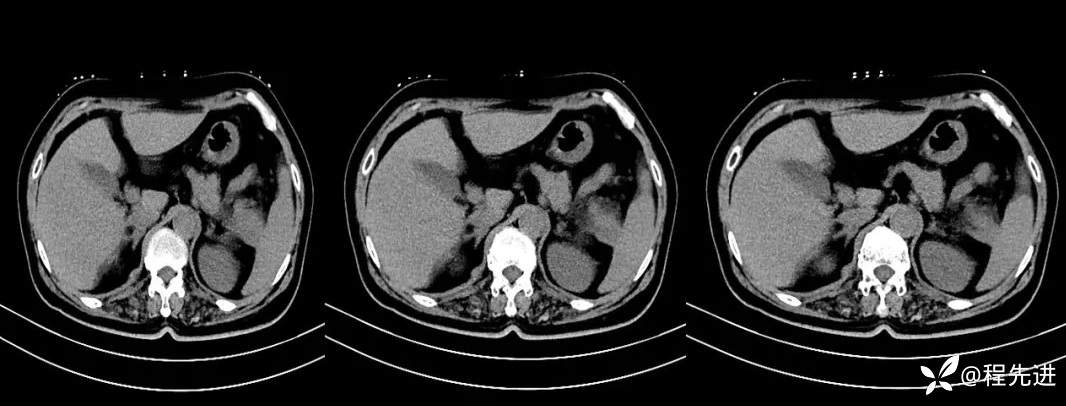

【现病史及既往史】:体检发现胰尾部肿块4年,当时手术病理提示异常增生性病变,现发现右侧顶部包块,逐渐增大,无明显感觉不适

影像检查: